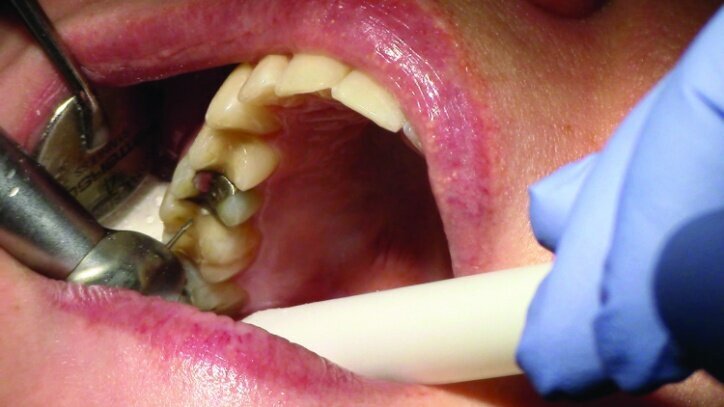

Depth guide cuts were made using a 330 bur, which has a 2 mm cutting surface (Figs. 2a–3b). This ensures 2 mm of occlusal reduction to accommodate 2 mm of material thickness on the occlusal surface of the restoration.

Gross occlusal reduction was completed using a KS7 bur to the depth cuts (Figs. 4–8b, 9c). Adequate clearance was verified with a 2 mm prep check from Common Sense Dental Products.